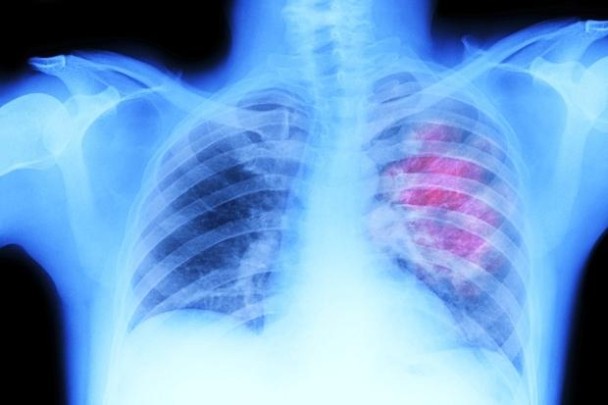

英国最新研究发现接受胸腔放射治疗 末期小细胞肺癌患者有望增加存活率

(神秘的地球报道)英国最新研究发现,患上末期小细胞肺癌(SCLC)的患者,若接受胸腔放射治疗,有望增加存活率。

英国癌症研究学院让498名来自英国、荷兰、挪威和比利时,曾接受初步化疗并见效的SCLC患者,分别接受2星期的一般放射治疗和胸腔放射治疗。结果发现,接受胸腔放射治疗的患者,2年后有13%仍然健在,而接受一般治疗的患者,则只有3%仍然存活。

研究又发现,接受胸口放射治疗者存活半年而病情没恶化的达24%,较接受一般放射治疗的多出17%。研究人员认为胸腔放射治疗是治疗肺癌的新突破,有关研究刊登于医学期刊《刺针》。